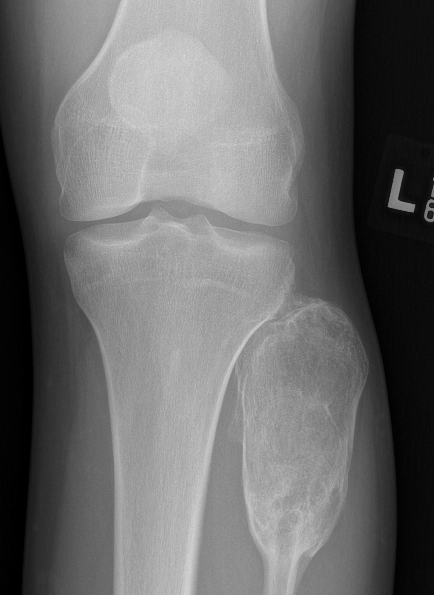

X-ray

Multi-loculated expansile lesion with cortical thickening

Often fail to make definitive diagnosis on xray